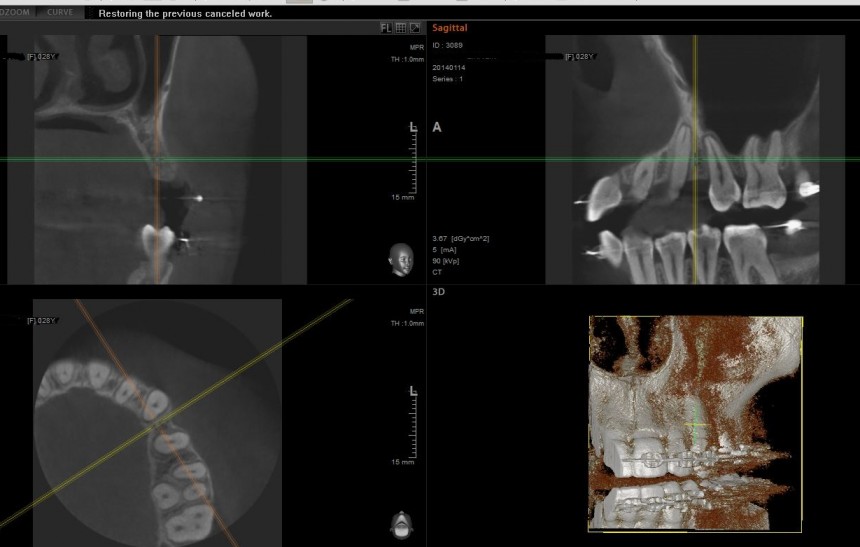

Основными методами обследования перед операцией являются ортопантомография и конусно-лучевая компьютерная томография (рис 12 и 13).

Рисунок 13. Интерфейс программы конусно-лучевой компьютерной томографии. Именно КЛКТ дает наиболее полное представление о клинической ситуации и позволяет правильно спланировать оперативное вмешательство.

Золотым стандартом в обследовании пациентов, которым планируется операция синуслифтинга, является проведение конусно-лучевой компьютерной томографии. Анализируюя ее, можно не только определить пространственную конфигурацию верхнечелюстной пазухи, но и выявить анатомические структуры, которые могут повлиять на ход оперативного вмешательства. Более того, современные программы КЛКТ позволяют оценить состояние слизистой оболочки гайморовой пазухи.

Нужно ли говорить, что это всё это является важным при планировании операции синуслифтинга?

Анализ клинической ситуации

Конусно-лучевая компьютерная томография позволяет не только субъективно оценить состояние области предполагаемой операции, но и провести расчеты, необходимые для ее планирования.

Для этого производятся необходимые измерения. Основное значение имеет расстояние от нижней точки дна верхнечелюстного синуса до наиболее выступающей точки альвеолярного гребня, проведенное перпендикулярно плоскости смыкания зубов (рис 15):

Рисунок 15. Расстояние между точками А и В является основным критерием планирования операции.